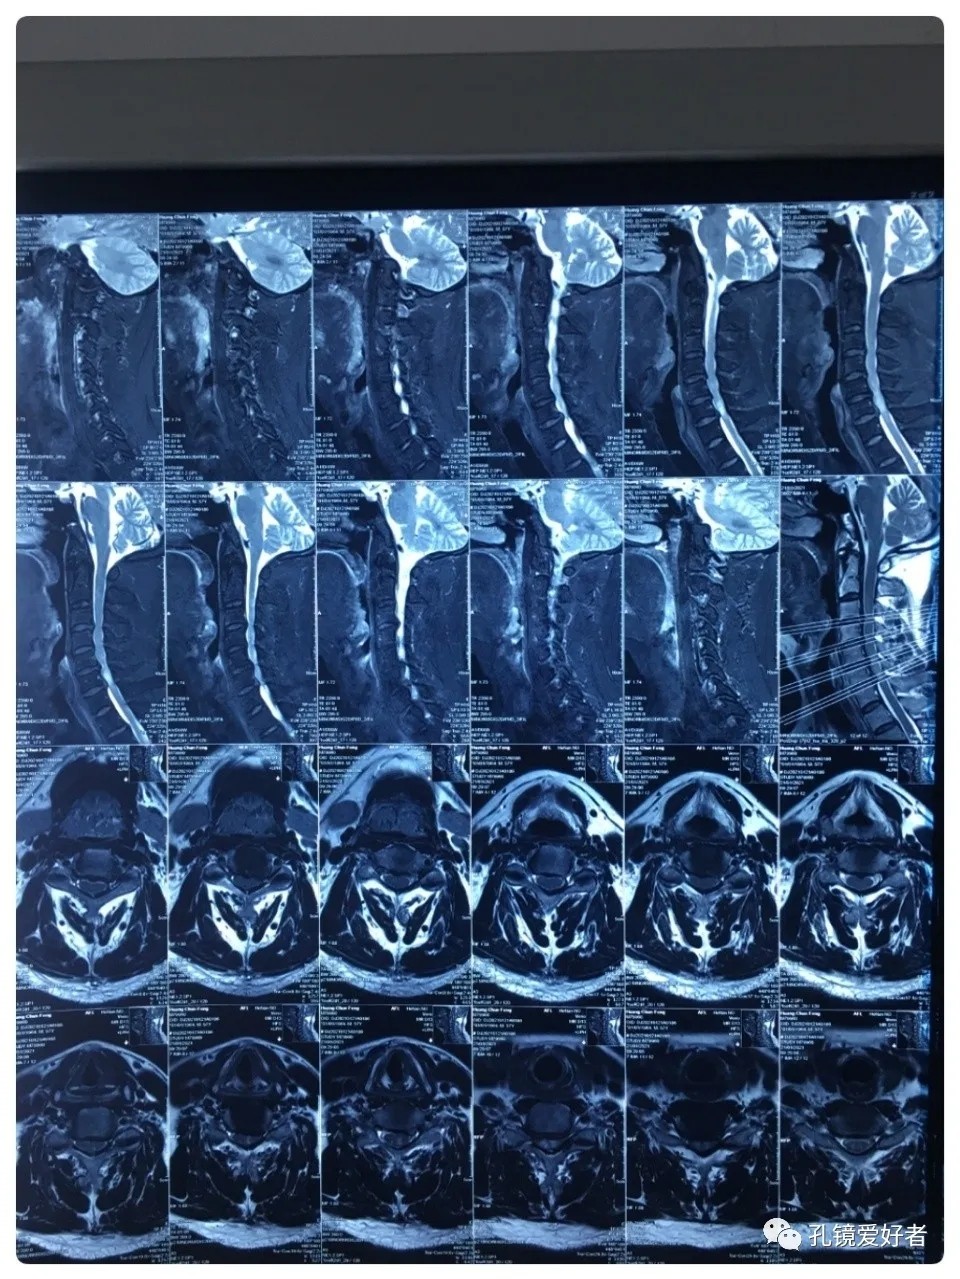

The patient's preoperative imaging data

Then let's look at MRI.

The MRI shows that the cervical stenosis is on C3-4, C5-6 and C6-7. Considering the patient's clinical symptoms, C5-6 and C6-7 are the main affected segments. So it’s advised that the patient undergo posterior cervical open-door laminoplasty. According to the patient, he had visited many hospitals before and received similar proposals of diagnosis and treatment- posterior cervical open-door laminoplasty. The reason he came to our hospital was that he wanted his surgery could be performed in a minimally invasive way. After considerable preoperative discussion with my colleagues and the patient, we decided to perform the minimally invasive endoscopic decompression for C5-6 and C6-7 double-segment stenosis through posterior approach (with the Delta system).

No thoracic lesion was identified before the surgery.